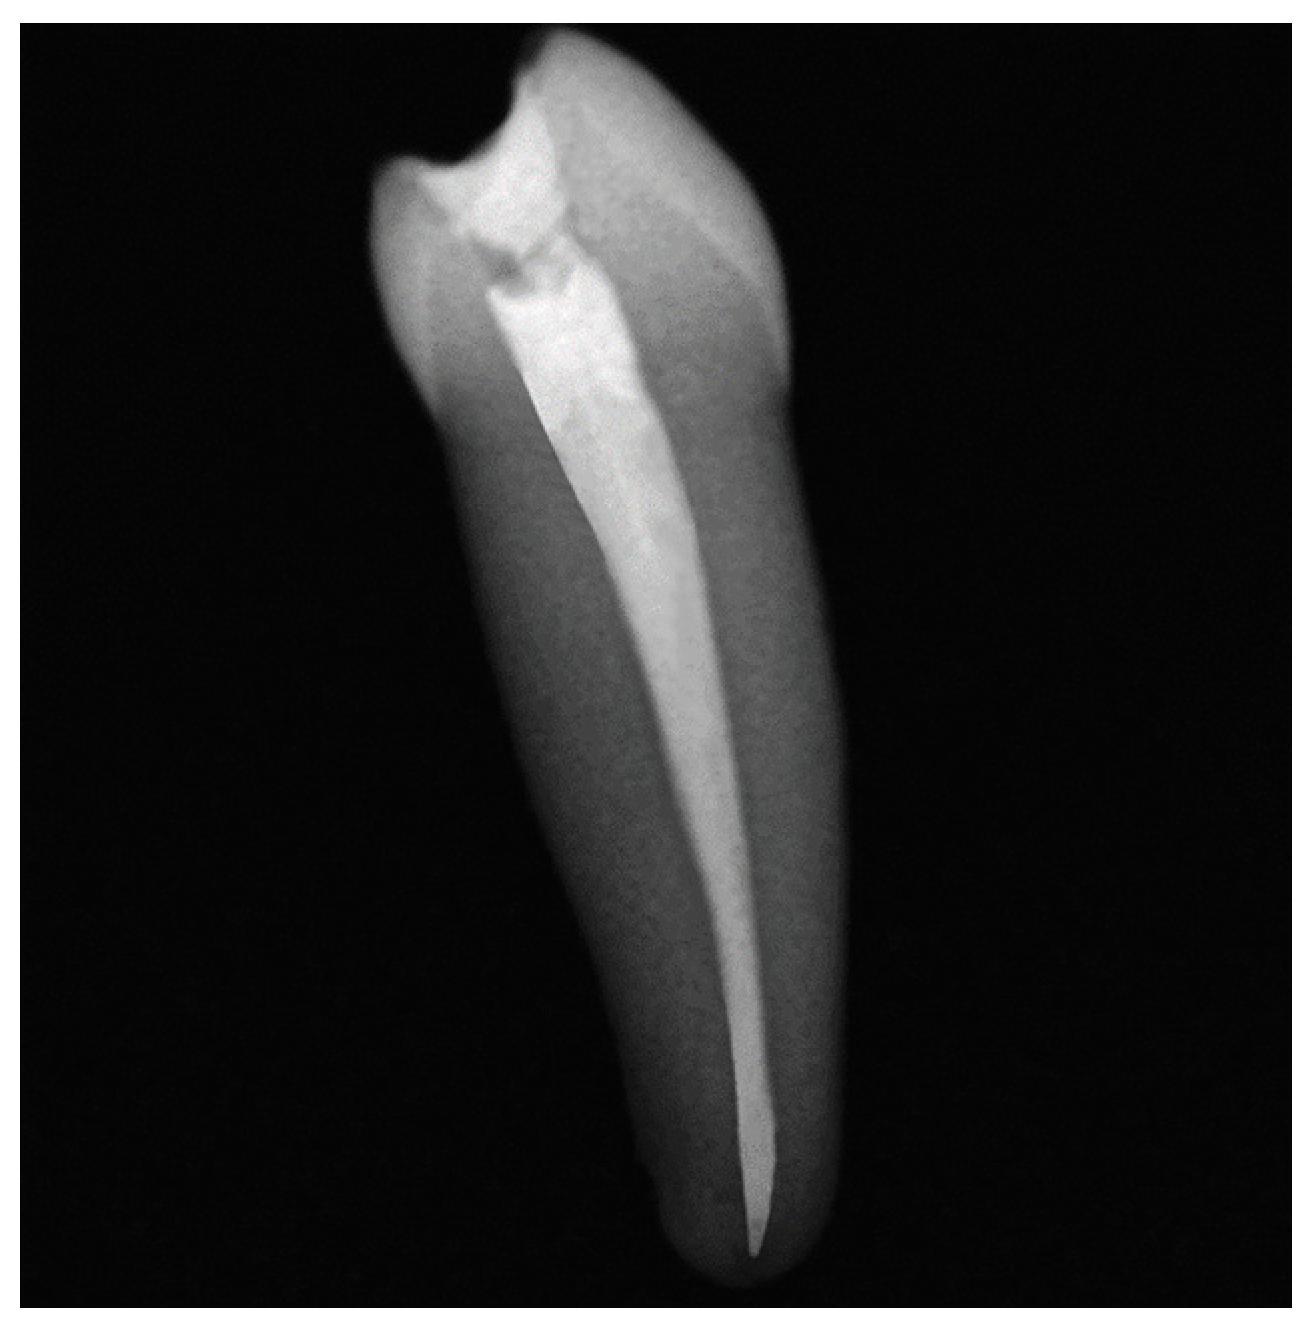

2.2. Specimen Preparation